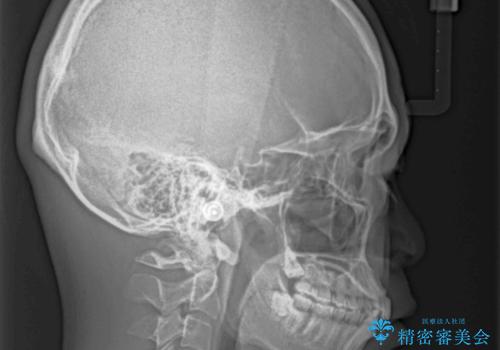

- 上下前歯のデコボコと下の前歯が隠れるほどの深い咬み合わせを気にして来院された患者様です。

インビザラインによる上下歯列の拡大と、IPR(歯と歯の間を削る)にるスペースの獲得により、口元のデコボコとディープバイトを改善することとしました。

デコボコがなくなったことで日頃の清掃が行いやすくなり、深い咬み合わせが改善したことで、食いしばりによる顎の負担も軽減されました。